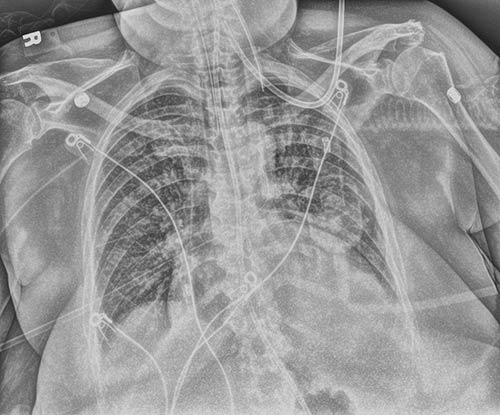

Modificata

Sicurezza con una singola esposizione. Il miglioramento Tube & Line crea un’immagine complementare e utilizza un’elaborazione ottimizzata per una visualizzazione più nitida e semplice delle linee e delle cannule PICC. Questo aumenta la sicurezza che le cannule e le linee siano posizionate correttamente e rimangano in posizione.